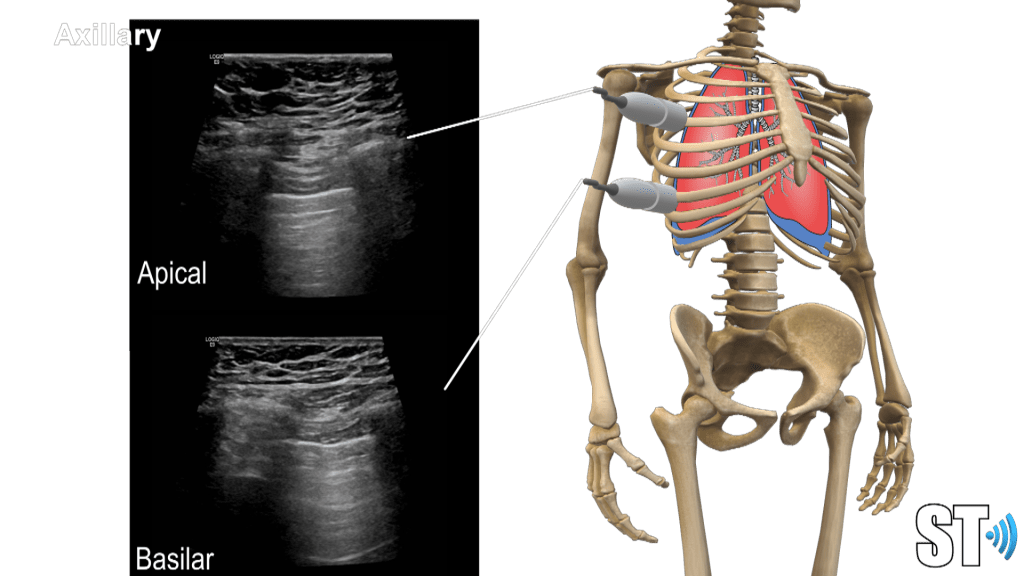

Using a linear, sector or small curvilnear transducer, divide the chest into parasternal, anterior and posterior axillary lines. Scan the basilar, mid and apical or upper portions of the chest. Scan the posterior aspect of the chest also at the base, mid and superior portions.

Anterior

Axillary

Posterior